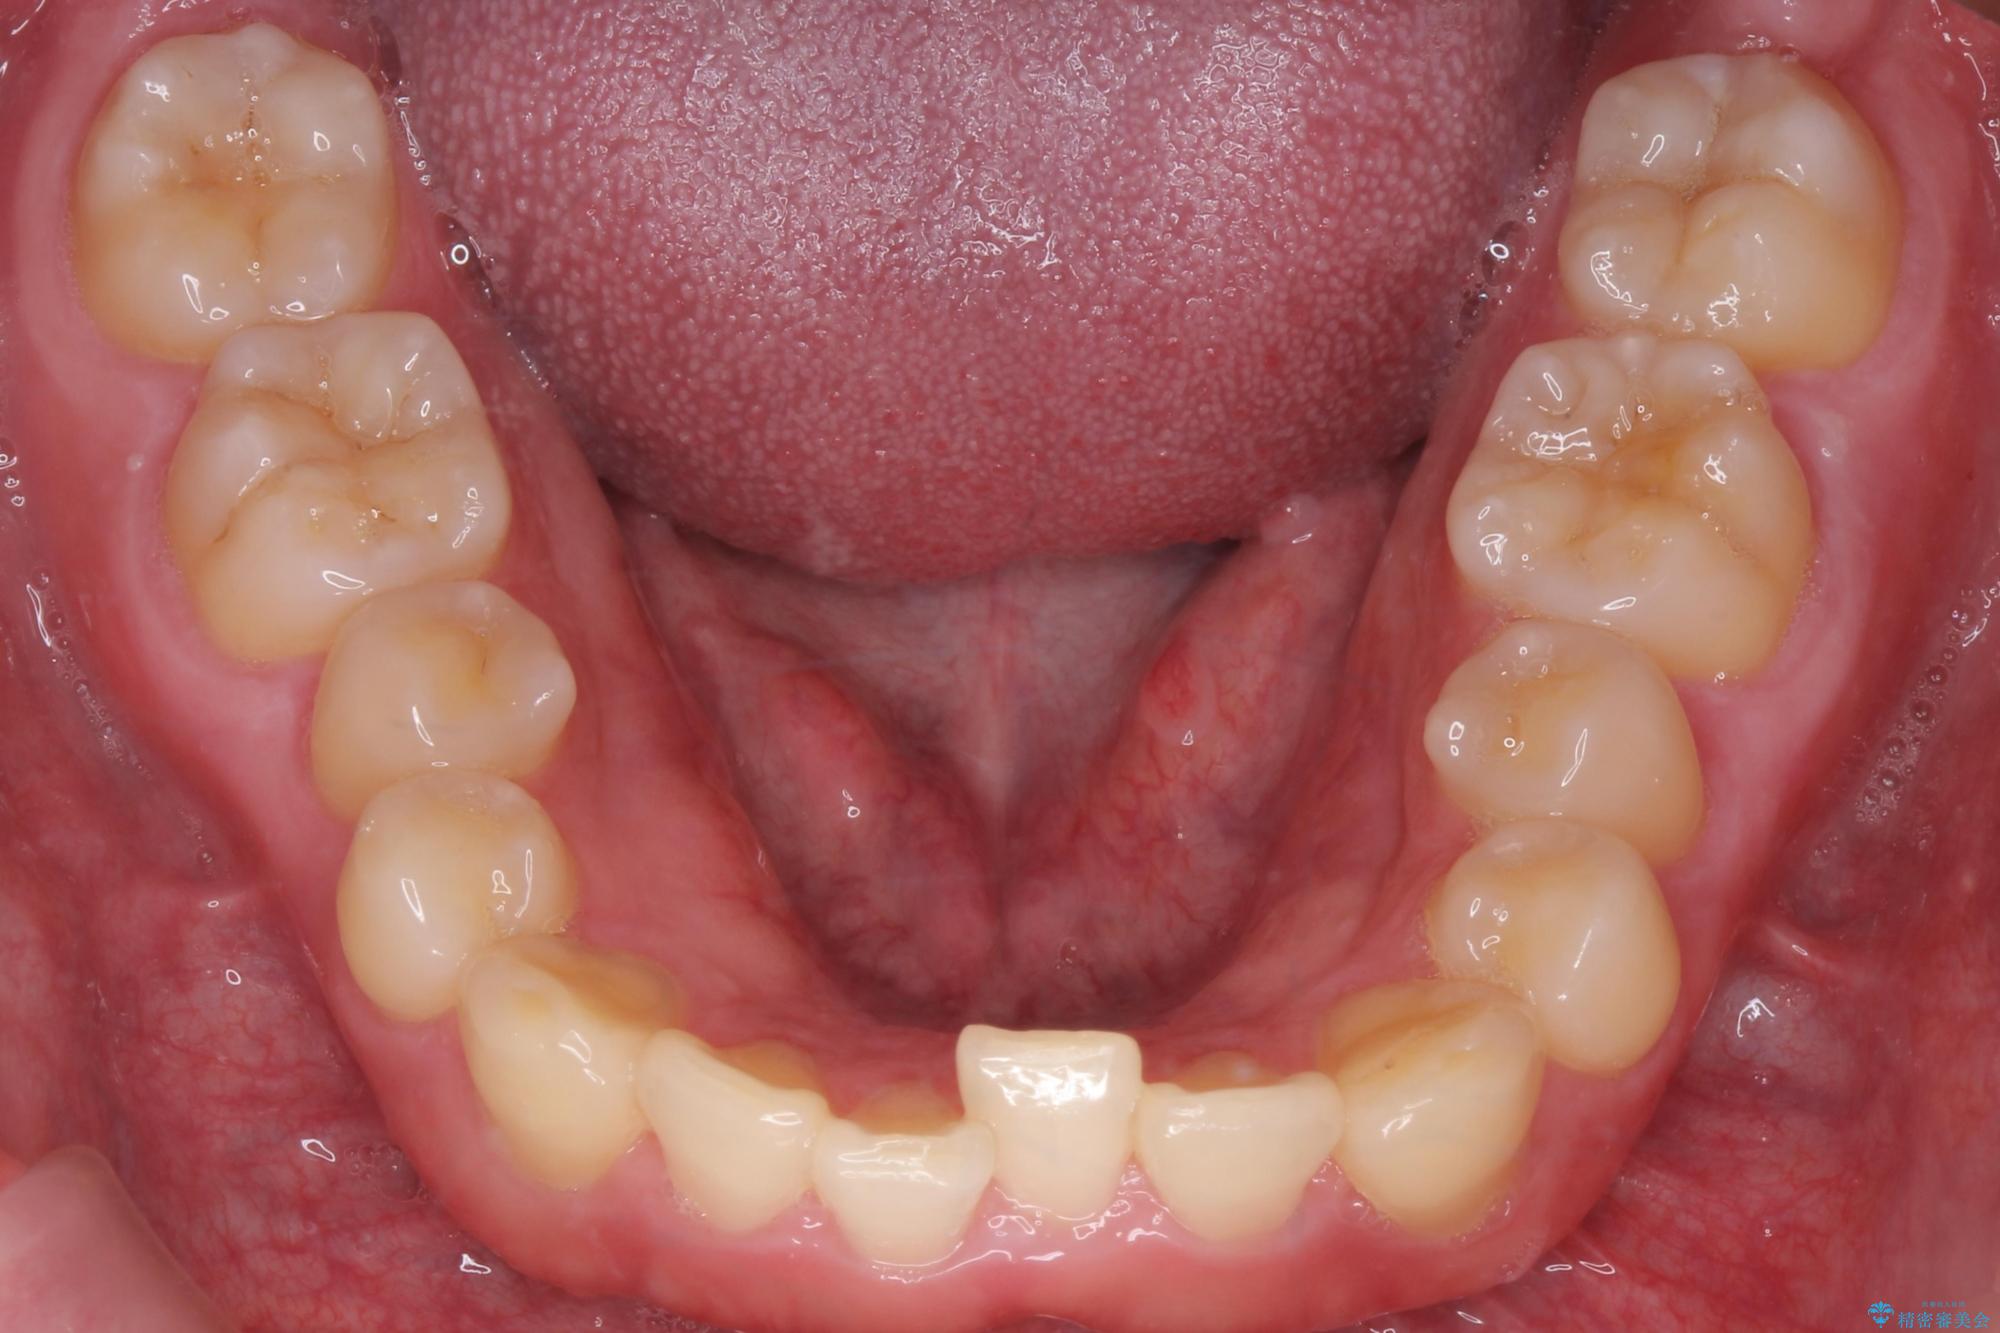

下の歯のがたつきが気になるとご来院されました。

左上の奥歯がシザーバイトがありました。

部分矯正を行いシザーバイトを改善した後、インビザラインで歯列を整えました。